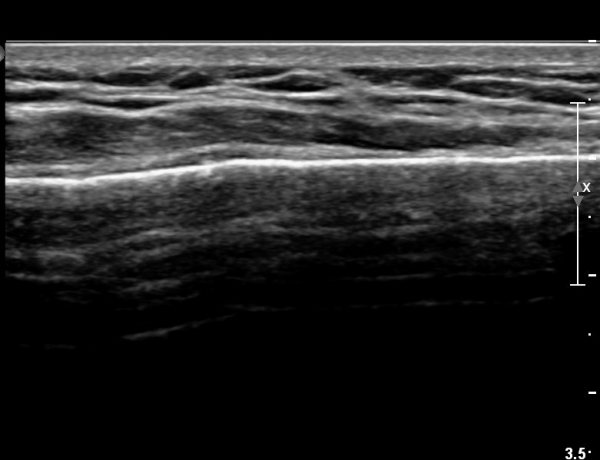

ŽÃËÀÚ¸¦ ¾à°£ ¸»´ÜÀ¸·Î À̵¿ÇÏ´Ï ¿¬ºÎÁ¶Á÷ ºÎÁ¾ÀÌ ´õ¿í ½ÉÇÏ°Ô °üÂûµÇ°í(»çÁø 2),